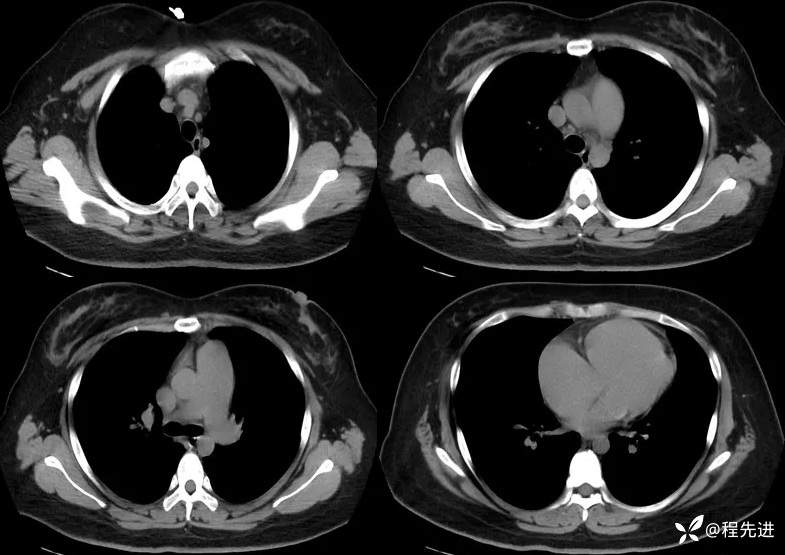

一月余后CT:

患者性别:女

患者年龄:26岁

主诉:咳嗽气促11个月

现病史:患者11个月前无明显诱因下出现咳嗽,无痰,干咳为主,伴有胸闷、气促,活动后加重,无发热,畏寒及胸痛、咯血、晕等,曾在外院治疗,诊断为特发性肺动脉高压。